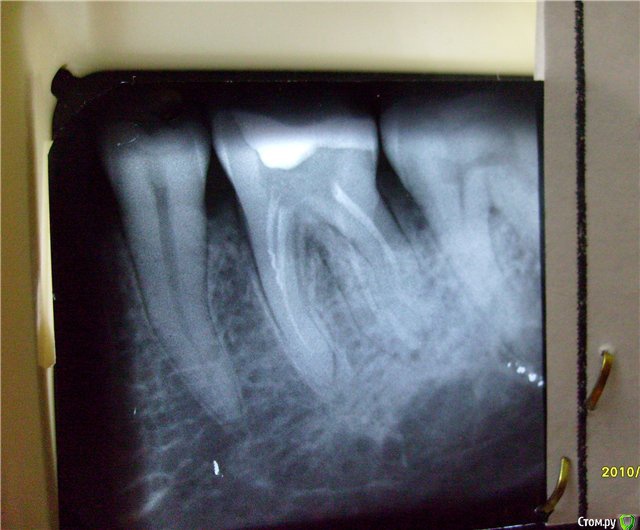

Slaggy Опубликовано 27 декабря, 2014 Поделиться Опубликовано 27 декабря, 2014 Пользовался китайским эндомотором - можно работать при отсутствии чего-то другого.Вполне себе приятное соотношение цена/качество.Сейчас работодатель подогнал Antogyr NiTi control - ничетак, но не в восторге.До этого на одной работе был 70:1 угловой наконечник - это ад. Пришлось уволиться.X-Smart лучшее из того, что в руки попадало. Хотя китаец был с апекслокатором - это очень добавляло к приятности работы. Короче я за китайские моторы )))) Поупайте, работайте ага, вот снимочек после китайца с апекслокатором 22 recall 1 год 1 Ссылка на комментарий